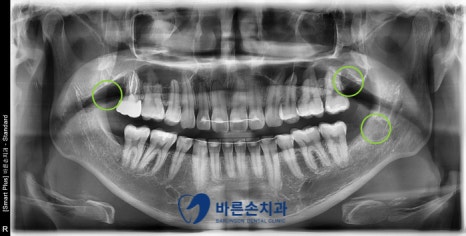

전체 검사 결과,

충치치료 2개와 사랑니 발치가 필요하다는 진단이 나왔습니다.

사진에서 보시면

★ 오른쪽 위 두번째 큰 어금니는 인접면 우식이 심하게 진행 -> 신경치료와 크라운

■ 오른쪽 아래 첫번째 큰 어금니의 교합면 우식 -> 인레이

● 오른쪽 위와 왼쪽 위아래 사랑니의 교합면 우식 -> 발치

치료가 필요한 상황입니다.